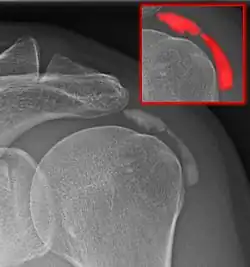

Calcific bursitis refers to calcium deposits within the bursae. This most occurs in the shoulder area. The most common bursa for calcific bursitis to occur is the subacromial bursa. A bursa is a small, fluid-filled sac that reduces friction, and facilitates movements between its adjacent tissues (i.e., between tendon and bone, two muscles or skin and bone). Inflammation of the bursae is called bursitis.